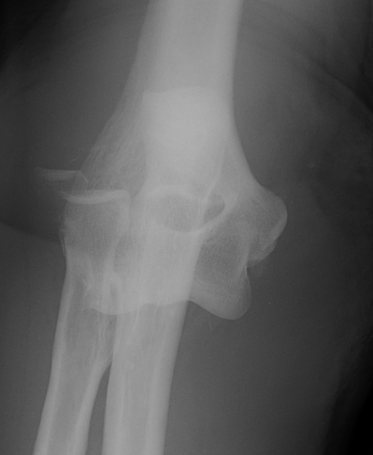

Ulna collateral ligament injury

6 /100 000

- second most common dislocation after shoulder

FOOSH